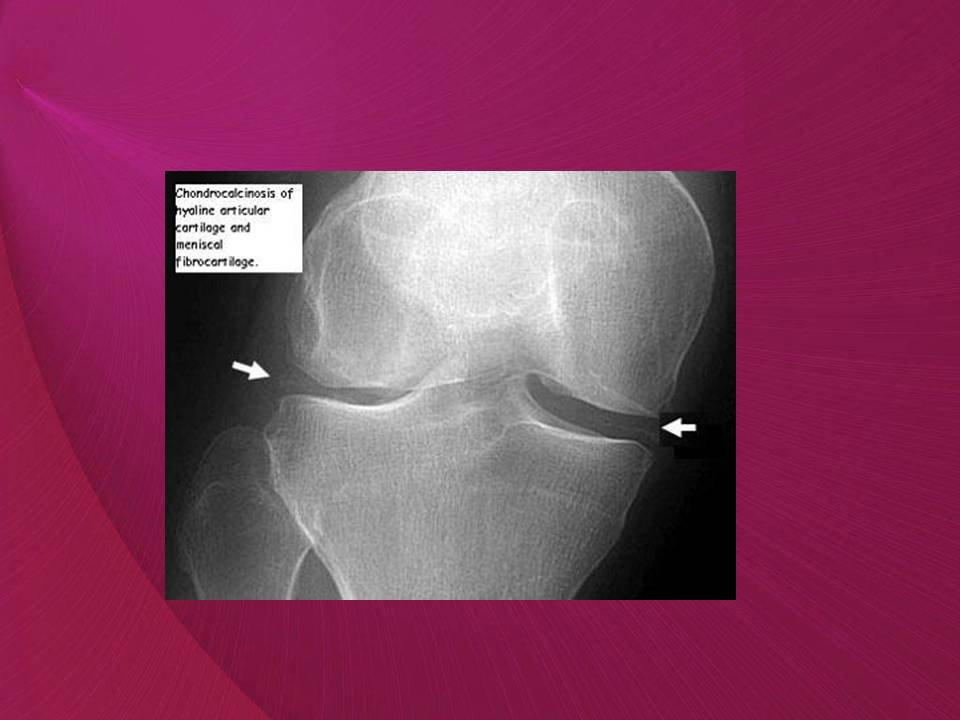

Rheumatic emergencies